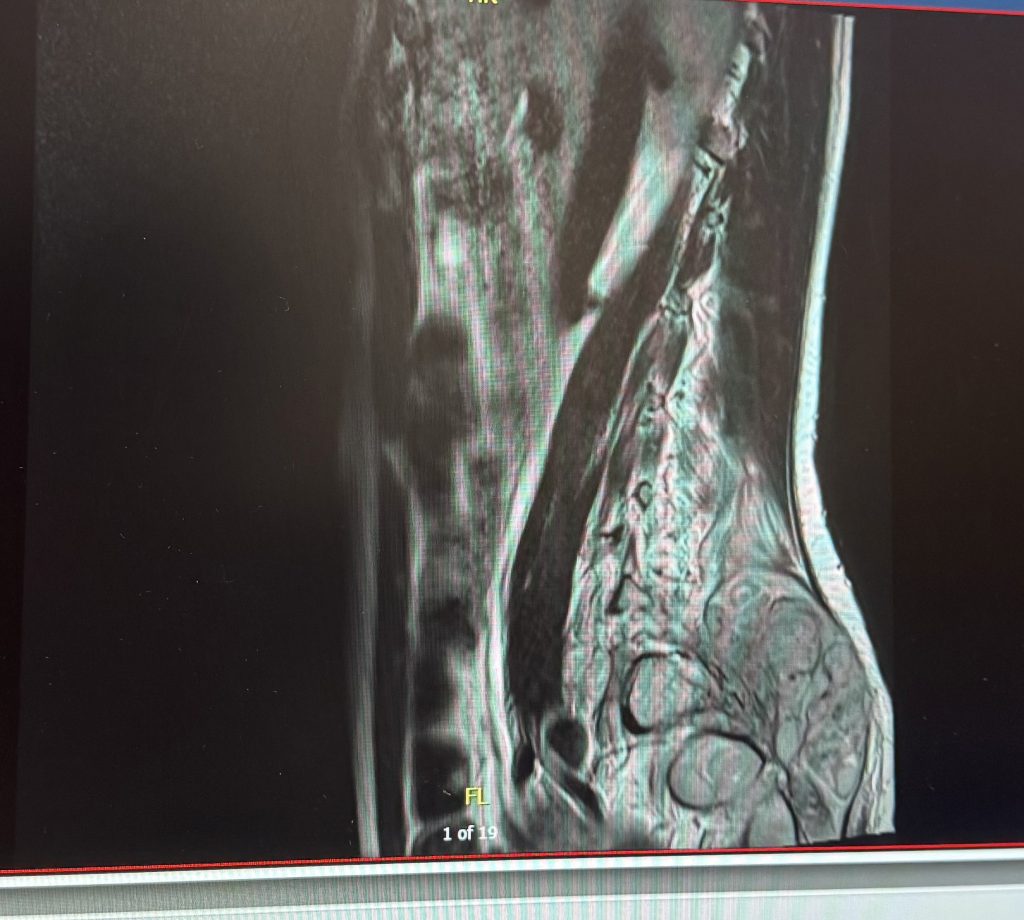

But when a tender, hard lump “the size of a grapefruit” appeared, Leah knew something was seriously wrong, and ended up flying to Greece to have an X-ray and MRI scan.

Her boyfriend, who grew up in Greece, booked a short trip to take her there to have MRIs and an X-ray, which found abnormalities.

Once again, Leah paid for a private consultation with a neurosurgeon to look at the scan results from Greece – and they were immediately concerned that it was a tumour.